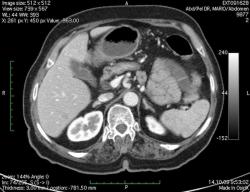

КТ брюшной полости. Женщина 73 года с жалобами на запоры.

Пациентка женщина 73 года. Предъявляет жалобы на запоры, спастические боли в брюшной полости.

ИзображениеЦиркулярное сужение в поперечной ободочной кишке. Ни это ли причина проблемм?

Причина именно в этом. Интересно, а ирригоскопию делали пациентке? На мой взгляд было бы показательно.

Новообразование в среднем отделе поперечной ободочной кишки с циркулярным сужением просвета и хронической механической толстокишечной непроходимостью. Признаков метастазирования в данной анатомической области не обнаружено. Пациент безусловно нуждается в хирургическом лечении.

Я не занимаюсь КТ, но сам характер сужения толстой кишки как-то вызывает сомнения, ракового ли он характера? Сужение то циркулярное, но больно уж ровненькое и нет признаков инфильтрации вокруг (хотя рак, конечно может иметь и такой вид). Ну, думаю dr.Mario со временем откроет карты и будет дана гистология.

Циркулярная стенозирующая опухоль (аденокарцнома) толстого кишечника; с типичной КТ презентацией и признаками обструкции. Пациентка была оперирована на второй день после КТ.

Коллеги, выполнять ирригоскопию после КТ, это нонсенс. КТ позволяет не только диагностировать опухоли/полипы кишечника, но и оценить окружающие органы, провести стадирование процесса.